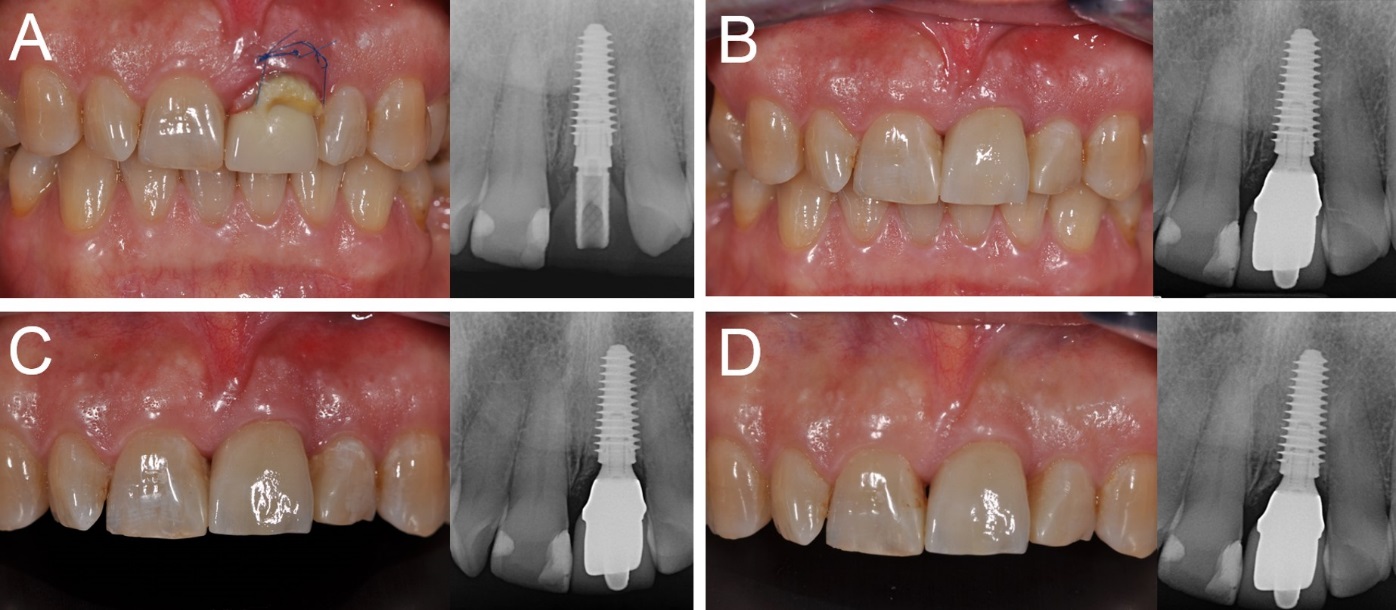

Overall, five patients could not attend the 4-year control visit and were therefore classified as drop-outs, despite the fact that the implants were still in operation. However, 4 years after insertion, only one implant was lost, in the posterior maxilla (second premolar, healed site) of a smoking woman, 48 years old at the time of surgery. The failed implant was 3.5 mm in diameter and 10.0 mm in length and was installed in bone type III. This implant failed during the first healing period, exactly two months after the insertion and immediate functional loading, as it lost stability, in the absence of infection. All the other implants were stable; therefore, the overall 4-year implant survival rate was 97.6% (patient-based, with 40/41 fixture in the survival category) and 98.1% (implant-based, with 51/52 implants in the survival category), respectively (Figures 1-4).

Figure 1.Immediate loading of a central maxillary incisor (#21) placed in a fresh extraction socket: (A) The implant is placed immediately after tooth extraction and loaded immediately after surgery; (B) three months later, the final metal‒ceramic crown is delivered; (C) the 1-year clinical and radiographic control; (D) the 4-year clinical and radiographic control.